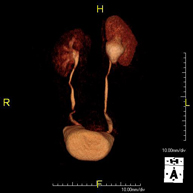

Prova diagnòstica no invasiva que consisteix en l'obtenció d'imatges d'alta definició anatòmica del fetge mitjançant l'ús d'un camp electromagnètic i ones de ràdio (amb un emissor i un receptor). No utilitza radiació ionitzant. Es realitza per estudiar qualsevol lesió localitzada en el fetge. Normalment es requereix l'ús de contrast paramagnètic (Gadolini) per caracteritzar les lesions. És necessari realitzat la prova en dejú (6 hores). - RM de Ronyons

Prova diagnòstica no invasiva que consisteix en l'obtenció d'imatges d'alta definició anatòmica d'ambdós ronyons mitjançant l'ús d'un camp electromagnètic i ones de ràdio (amb un emissor i un receptor). No utilitza radiació ionitzant. Es realitza per estudiar qualsevol lesió localitzada en ambdós ronyons. Normalment es requereix l'ús de contrast paramagnètic (Gadolini) per caracteritzar les lesions. - RM de Glàndules Suprarenals

Prova diagnòstica no invasiva que consisteix en l'obtenció d'imatges d'alta definició anatòmica de les dues glàndules suprarenals mitjançant l'ús d'un camp electromagnètic i ones de ràdio (amb un emissor i un receptor). No utilitza radiació ionitzant. No necessita preparació prèvia. No requereix l'ús de contrast paramagnètic (Gadolini). Està especialment indicada en aquells pacients en els quals és imprescindible diferenciar el nòdul suprarenal benigne (l'adenoma suprarenal és el més freqüent) d'altres lesions suprarenals (tant benignes -hematomes, angiomiolipomas, etc.- com malignes). - RM de Melsa